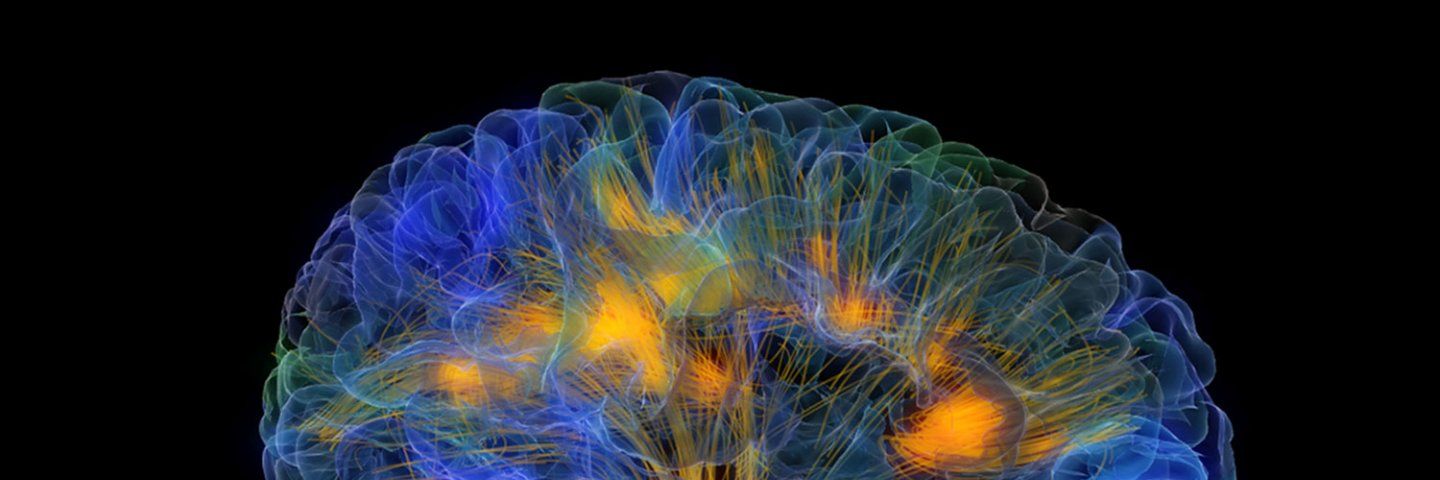

Researchers and clinicians at the UCSF Weill Institute for Neurosciences are working together to find better ways of monitoring, maintaining, and even enhancing brain health across the lifespan.

From autism to anxiety to Alzheimer’s, neurological and psychiatric disorders are among the most complex health challenges we face today. New technologies for observing and interacting with the brain and nervous system are changing how we understand and care for these diseases.